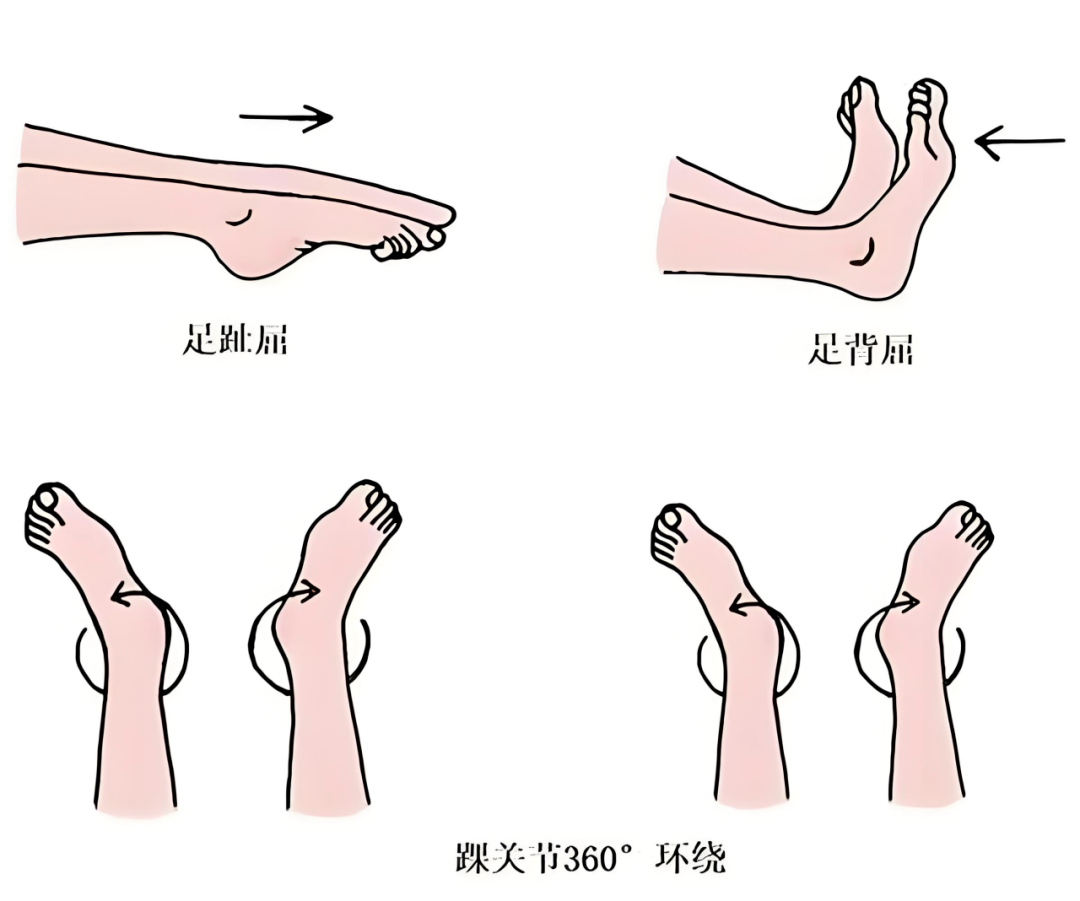

1.24小时内练肌肉收缩:术后24小时内,可在床上做四肢肌肉等长收缩练习,比如踝泵运动(做足趾屈、足背屈、踝关节360°环绕动作)、股四头肌收缩练习,预防深静脉血栓和避免肌肉萎缩。

踝泵运动